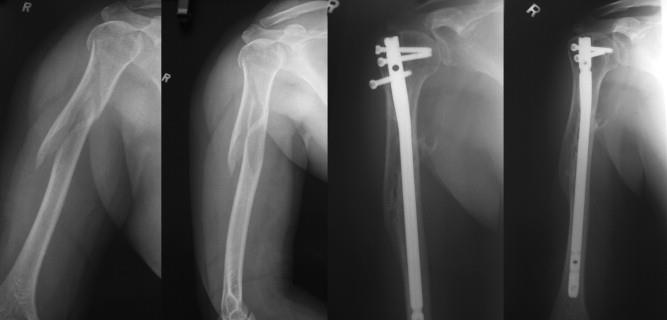

• The T2 Alpha® Humerus Nailing System is an intramedullary fixation system designed for stable treatment of humeral shaft and proximal humerus fractures

• The system is engineered to support accurate alignment, controlled compression, and reliable fracture healing

• straight nail design allows for alignment of the epiphyseal fragment with the diaphysis and gives structural support to the humeral head fragment